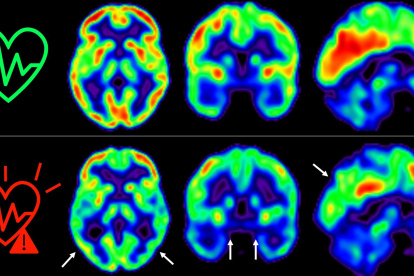

Cuidar la salud cardiovascular es bueno también para el cerebro